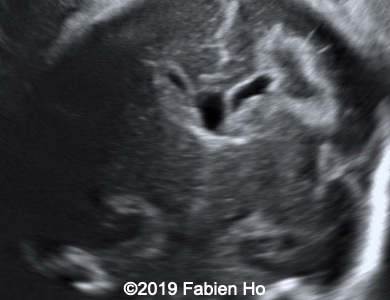

Images 1-3: in the left frontal lobe, hyperechoic with hypoechoic center lesion within the deep and periventricular white matter. Interestingly, this lesion has no mass effect on the lateral ventricle, and it has smooth margins.

Images 12-16: we performed a second fetal brain MRI at 32 weeks, which showed the same findings as the postnatal neonatal brain MRI as follows:

The evolution of the images is typical of a clastic lesion: after resorption of the ischemic tissue and hematoma, there was now a focal porencephaly with hemosiderin tattooing on its margins. Conversely, persistence of the same MRI findings would have indicated an hypercellular brain tumor, which could have been a differential diagnosis.